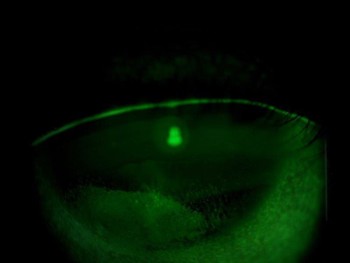

The patient was a 30-year-old male office worker I’d been managing for six months for evaporative dry eye disease. He had persistent corneal staining (Fig 1.) and suffered from significant corneal discomfort. In addition to consistent home therapy with warm compresses, omega-3 supplements and ocular lubricants, he received treatment with thermal pulsation using LipiFlow and quantum molecular resonance (QMR) with Rexon-Eye. Although his symptoms improved slightly with this treatment regimen, the corneal staining remained and he continued to experience significant discomfort.

Fig 1. Fluorescein slit lamp image of the right cornea at

presentation